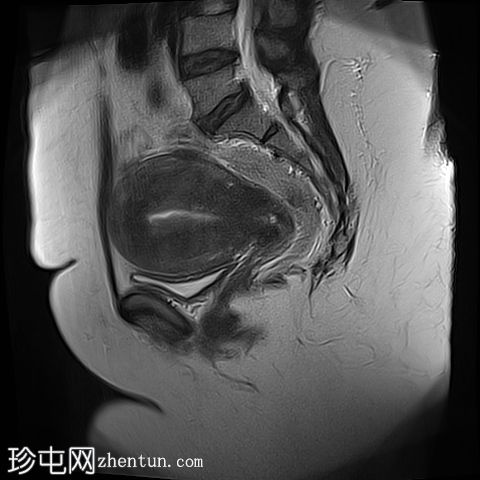

矢状位

T2加权像

子宫前倾且体积增大,交界区呈边界不清、弥漫性对称性增厚。T2加权像和T2脂肪抑制像均显示条纹状高信号,无异常强化或扩散受限。

子宫内膜腔、交界区和外层肌层边界不清。

子宫肌层前壁可见一小而边界清晰的实性病灶,大小为1.1 × 1.0 cm。该病灶在T1加权像上呈中等信号强度,在T2加权像上呈低信号强度,无强化,无扩散受限。

本病例展示了弥漫性子宫腺肌症的典型MRI特征,包括交界区弥漫性增厚和T2加权像上呈条纹状高信号区域。